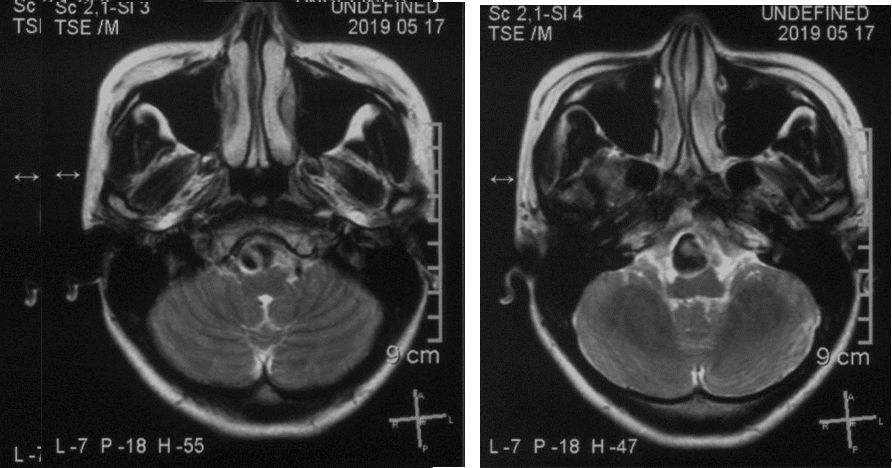

2019.5.17外院头颅MR

患者核磁共振显示脑桥-延髓前方流空影,考虑动脉瘤,有明显的双腔征,瘤壁有加强,且对脑干有一定的压迫。